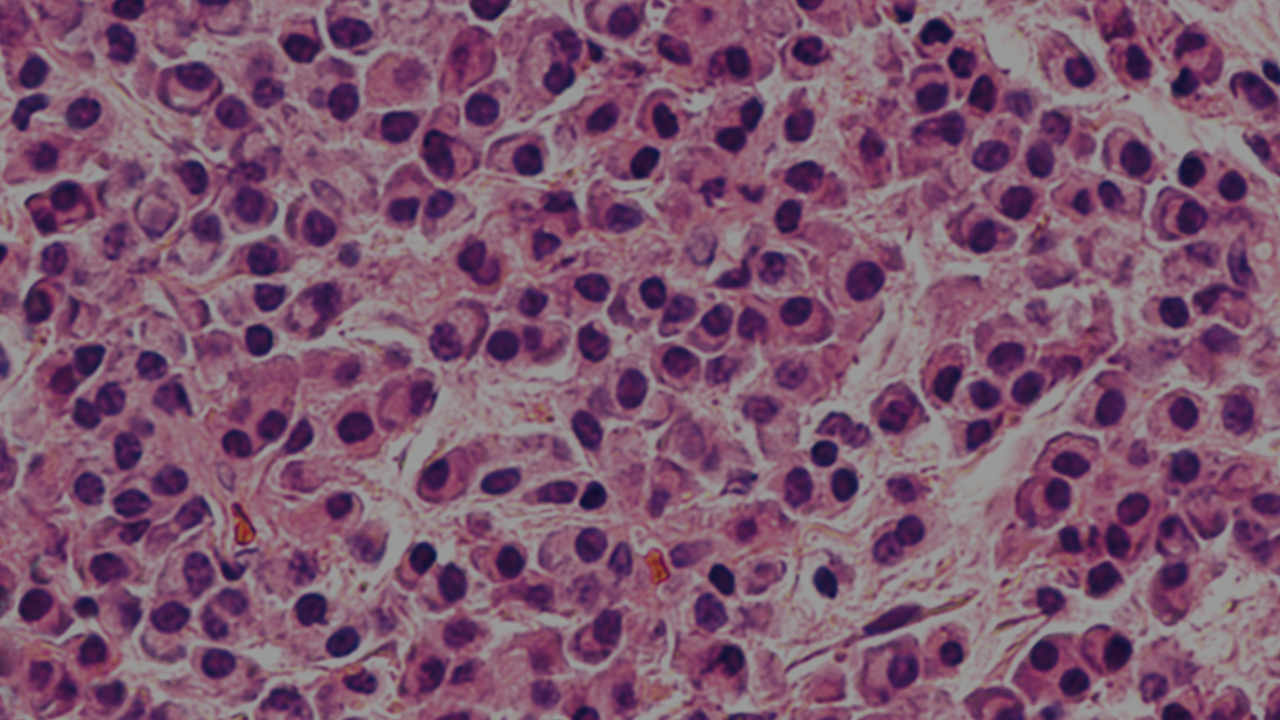

Patients should have at least 10% clonal bone marrow plasma cells or biopsy-proven bony or extramedullary plasmacytoma, and any one or more myeloma-defining events (CRAB and/or biomarker of malignancy).